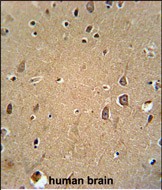

| IHC | 1/100-1/500 | Human,Mouse,Rat |

Antibodies targeting EphA6 are essential tools for investigating its expression, localization, and function. These antibodies are widely used in techniques such as Western blotting, immunohistochemistry, and flow cytometry to study EphA6's role in physiological and pathological contexts. Due to EphA6's potential as a therapeutic target or biomarker in diseases, specific and validated antibodies are crucial for preclinical research. Recent advances in antibody engineering have improved their specificity, enabling precise detection of EphA6 isoforms and post-translational modifications. However, challenges remain in distinguishing EphA6 from closely related Eph receptors, underscoring the need for rigorous validation in experimental models. Ongoing research continues to explore EphA6's mechanistic contributions to disease, driving demand for reliable immunological reagents.